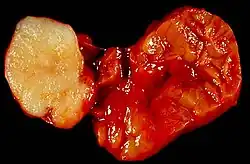

Benign tumour of the submandibular gland, also known as pleomorphic adenoma, presented as a painless neck mass in a 40-year-old man. At the left of the image is the white tumour with its characteristic cartilaginous cut surface. To the right is the normally lobated submandibular salivary gland.Warthin's tumor